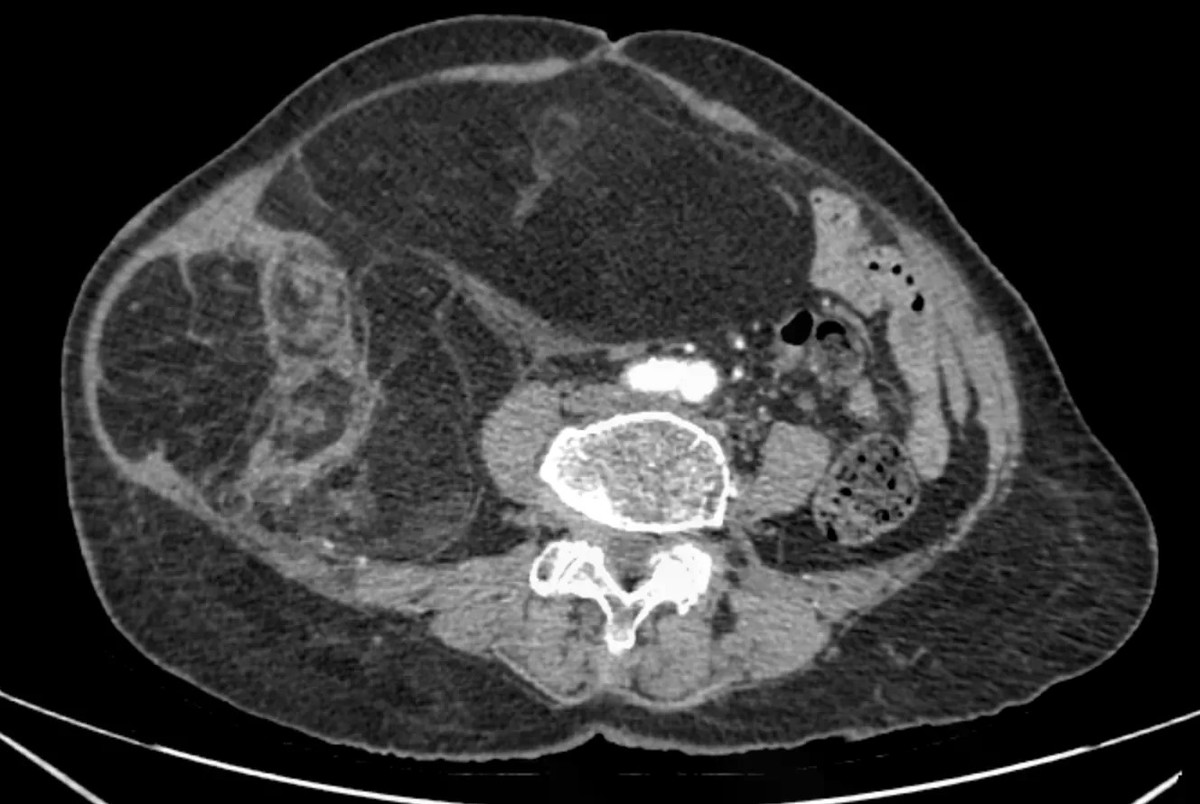

Chẩn đoán hình ảnh (CT ổ bụng có thuốc cản quang) cho thấy khối choán chỗ sau phúc mạc, kích thước 28 × 15 cm, cấu trúc hỗn hợp tổ chức mỡ – đặc, đè đẩy tạng trong ổ bụng nhưng không có dấu hiệu xâm lấn các tạng lân cận. Kết hợp lâm sàng và hình ảnh học, bệnh nhân được chẩn đoán sarcoma mỡ sau phúc mạc.

Hình ảnh khối u trên phim chụp CT ổ bụng - Ảnh BVCC